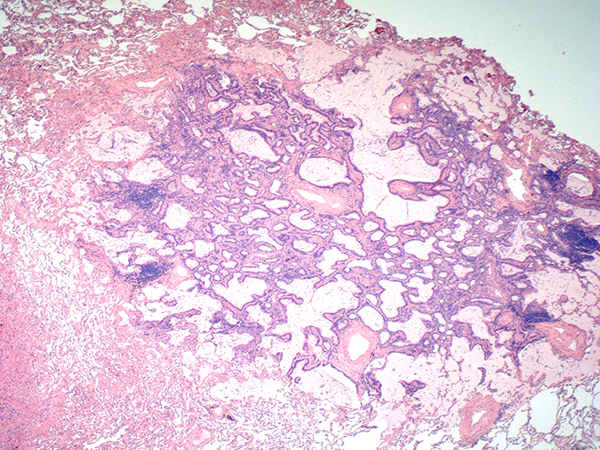

Clinical History: A 75 year old female with a history of a previously resected right upper lobe pulmonary adenocarcinoma presented with two nodules in the left upper lobe 14 years later. The patient underwent a left upper lobe wedge resection encompassing both radiographic nodules. Grossly, distinct 10.0 mm and 4.0 mm nodules were identified. The larger nodule was a classical non-mucinous acinar predominant adenocarcinoma; however, the smaller nodule had a different appearance, as illustrated in Figures 1-6.

Take home message for trainees: CMPT is a rare but increasingly recognized neoplasm of the lung which may be easily mistaken for mucinous adenocarcinoma. The bi-layered tumor morphology consisting of ciliated and mucinous cells overlying a uniform row of basal cells is a unique feature of CMPT which should aid in identification.